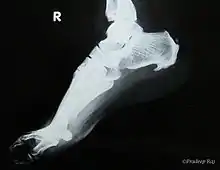

| A radiograph showing osteophytes on the posterior and inferior aspects of the calcaneus | |

A calcaneal spur (also known as a heel spur) is a bony outgrowth from the calcaneal tuberosity (heel bone).[1] Calcaneal spurs are typically detected by x-ray examination.[2] It is a form of exostosis.

An inferior calcaneal spur is located on the inferior aspect of the calcaneus and is typically a response to plantar fasciitis over a period, but may also be associated with ankylosing spondylitis (typically in children). A posterior calcaneal spur develops on the back of the heel at the insertion of the Achilles tendon.[3]

An inferior calcaneal spur consists of a calcification of the calcaneus, which lies superior to the plantar fascia at the insertion of the plantar fascia. A posterior calcaneal spur is often large and palpable through the skin and may need to be removed as part of the treatment of insertional Achilles tendonitis.[3]

Spur outgrowths can be detected through physical exam followed by a lateral foot x-ray.